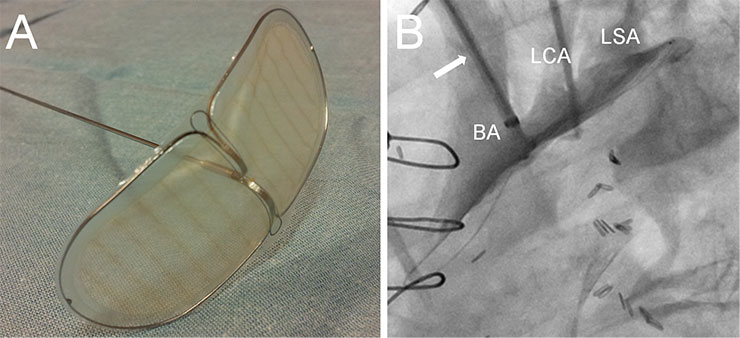

Figure 4

Example of an embolic protection device. The Embrella embolic deflector (A, Embrella Cardiovascular Inc, Wayne, PA) is introduced through the right radial artery to protect the brachiocephalic artery (BA), the left carotid artery (LCA) and the left subclavian artery (LSA) during the procedure.

Different embolic protection devices are currently in use and under investigation [57–59]. These devices are introduced at the beginning of the procedure either through the right radial or the femoral artery and their aim is to protect the brachiocephalic and left carotid artery from embolic material (fig. 4 ). An ideal protection device would be minimally invasive, easy and rapid to use with minimal risk of vascular injury, and should not interfere with the actual TAVI procedure. The current devices are composed of a thin membrane with pores of about 100–200 µm size designed to allow normal blood flow but deflect or capture embolic material. While these devices certainly have the potential to reduce cerebral embolism, experience with TAVI is limited [57]. As TAVI is currently performed in elderly patients who often have very calcified arteries, it is possible that deployment of the protection device itself results in embolisation of some debris. In the future these devices may become more important if TAVI is performed in younger patients with a less calcified aortic arch where the main source of embolism is the valve itself.